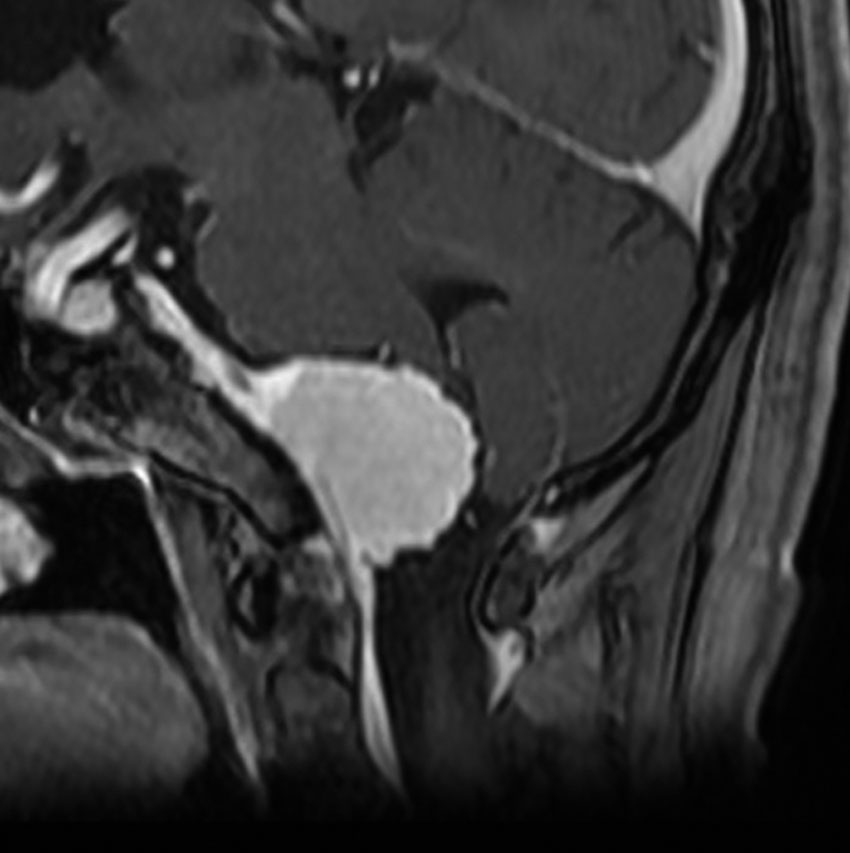

大後頭孔(大孔)髄膜腫 foramen magnum meningioma)

この腫瘍はfarlateral approachなどの頭蓋底手術をしなくても,外側後頭窩開頭で全摘出できます。要領は,S状静脈洞の下端の周囲骨を削除することです。大後頭孔髄膜種は延髄を圧迫するので巨大なものはありません。出血のコントロールや延髄からの剥離は比較的容易なものが多いでしょう。舌咽神経と迷走神経損傷を避けることが重点となります。

迷走神経と舌咽神経は機能温存できました。舌下神経が腫瘍の表面に薄く広がり剥がすことができずに半分以上を切断しています。でも片側舌下神経麻痺では日常生活に困ることはあまりありません。